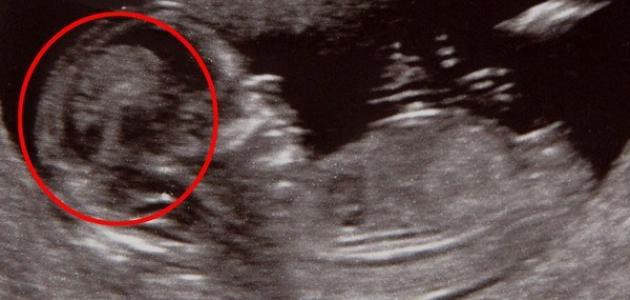

متى يظهر الجنين على السونار

إنَّ جهاز السونار أو Ultrasound من الأجهزة الَّتي أثبتت جدارتها عن حق، فقد ساعدت الإنسان على معرفة بعض التفاصيل الهامّة والتشخيصيّة على مستوى عميق من جسم الإنسان، الَّتي قد يكون لها تأثير كبير في تلقّيه للعلاج المُناسب، وواحدة من أهم استخدامات السونار هي: رؤية الجنين، ومعرفة جنسه، والتأكّد من صحّته وسلامته، ويعدّ توفر هذا الجهاز نعمة من الله تعالى، فقد ساعد الكثير من الأمهات والآباء على رؤية طفلهم قبل ولادته، والتأكّد من سلامته وصحّته، ويُمكن رؤية الجنين على السونار بدءاً من الأشهر الثلاث أو الأربع الأولى من الحمل، ففي تلك الفترة يمكن للوالدين رؤية طفلهما للمرَّة الأولى، وعادةً ما يُستخدم جهاز Transabdominal Ultrasound خلال فترة الحمل لرؤية الجنين.

يُمكن للعديد من السيدات الحصول على معلوماتٍ وافية عن الجنين من خلال جهاز Transabdominal Ultrasound ، وذلك بعد مرور أول ثمانية أسابيع من الحمل، ولكن خلال فترات الحمل الأولى المُبكّرة يكون حجم الجنين صغيراً، فقد يصل طوله في الأسبوع السادس من الحمل من خمسة إلى تسعة ملليمترات، وعندها قد يستخدم الطَّبيب جهاز سونار آخر وهوTransvaginal Ultrasound، وذلك للحصول على رؤيةٍ أوضح للجنين، ويُعدَّ جهاز Transvaginal Ultrasound آمناً، ويُمكن استخدامه خلال كافَّة مراحل الحمل ومنها الثُلث الأول من الحمل، والَّذي يُعدّ الثُلث الأكثر تأثّراً في الحمل، فهذا الجهاز لن يتسبّب في إيذاء الجنين أو الأم.